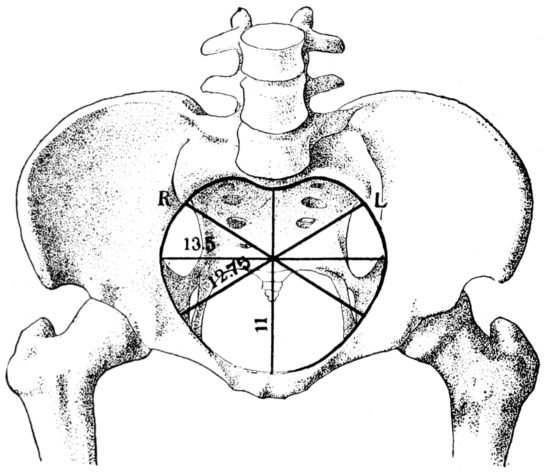

22The pelvic cavity as a whole is divided into the true and false pelves by a constriction of the entire structure known as the brim or inlet. The inlet is not round, its antero-posterior diameter being shortened by the sacro-vertebral joint which protrudes forward and gives the opening something of a blunt, heart-shaped outline. (Fig. 2.)

25In considering the question of pelvimetry, we find that there are both external and internal measurements to be taken, all for the purpose of estimating as accurately as possible the shortest diameter of the inlet through which the baby must pass. (Fig. 5.)

According to a common system of mensuration, the first external measurement is the inter-spinous, the distance between the anterior-superior spines, those bony points which are uppermost as the patient lies on her back. This distance is normally 26 centimetres. (Fig. 6.)

The second measurement is the inter-crestal, or the distance between the iliac crests, and is normally 28 centimetres.

Baudelocque’s diameter is the third measurement and is taken with the patient lying on her side. (Fig. 7.) It is the distance from the top of the symphysis to a depression just below the last lumbar vertebra. This depression is easily located as it also marks the upper angle of a space just above the buttocks, which in normal pelves is quadrilateral. In malformed pelves this quadrangle may be so misshapen as to become almost a triangle with the apex directed either up or down. This dimension 26is sometimes called the external conjugate and ordinarily measures 21 centimetres.

The fourth measurement is the distance between the great trochanters, or heads of the femora, and normally is 32 centimetres.

All of these measurements, which after all are only approximate, relate to the top of the pelvis and are valuable in that they help in estimating the dimensions of the inlet, which are the important ones, and obviously cannot be measured on a live woman.

Fig. 6.—Diagram showing method of measuring distances between iliac crests and spines and the trochanters.

The inlet has four measurements of obstetrical importance: the antero-posterior, or true conjugate, which is the distance from the top of the symphysis pubis to the prominence of the sacrum, and is normally 11 centimetres; the transverse diameter, which is at right angles to the true conjugate and is the greatest width of the inlet, measuring from a point on one side of the brim to the corresponding point on the other, is normally 13.5 centimetres, and the two diagonal measurements, known respectively 27as the right and left oblique diameters, which are normally 12.75 centimetres.

Although it is very important to the expectant mother that all of these dimensions be of normal length, the length of the true conjugate, or conjugata vera, is of the gravest importance of all because it is the shortest diameter through which the child’s head must pass. If it is shorter than normal, the channel may be too constricted for the full-term baby’s head to pass through comfortably, thus making a spontaneous delivery extremely difficult, or even impossible.

Fig. 7.—Diagram showing method of measuring Baudelocque’s diameter.

The length of the all important, true conjugate is estimated by introducing the first two fingers of one hand into the vagina until the tip of the second finger touches the promontory of the sacrum. (Fig. 8.) The point at which the inner margin of the symphysis then rests upon the forefinger is measured, thus giving the length of the diagonal conjugate. This normally measures 12.5 centimetres or more, and is estimated as being 1.5 centimetres longer than the true conjugate.

28The most important measurement of the outlet is the intertuberous diameter, the distance between the tuberosities of the ischii. This is the shortest diameter through which the child must pass in the inferior strait, and normally measures something more than 8 centimetres, usually about 11 centimetres. (Fig. 9.)

It is possible, by studying such measurements as these, made upon an expectant mother, and comparing them with dimensions which have been accepted as normal, to form a reasonably accurate estimate of the size and shape of her pelvis.

Fig. 8.—Diagram showing method of estimating the true conjugate by measuring the length of the diagonal conjugate.

A delivery may be, and frequently is, accomplished through a pelvis which is not entirely normal in size or shape. But the obstetrician of to-day is closely observant of the patient whose pelvic measurements depart from the normal by more than the accepted margin of safety, and he plans for labor in accordance with the indications in each case.

Disproportion between the measurements of the mother’s pelvis and the size of the child’s head must be considered in this connection. A small pelvis may permit of the spontaneous delivery of a small child, but be too narrow for the passage of a 29full-sized baby, while a woman with a normal pelvis may have an extremely difficult labor because of an unusually large child.

The size and shape of the pelvis is found to vary among different races and in different individuals. And the size and contour of the inlet may be so altered by rickets, lack of proper exercise during early life, or by growths upon the pelvic bones, as to seriously interfere with normal labor.

Fig. 9.—Diagram showing method of measuring the inter-tuberous diameter.

The various kinds of malformed pelves may be loosely classified as generally contracted or small; flat; simple funnel; generally contracted funnel; and the rachitic pelves, both flat and generally contracted. There may be a contracted inlet, or a contracted outlet, or both may occur in the same pelvis.[1]